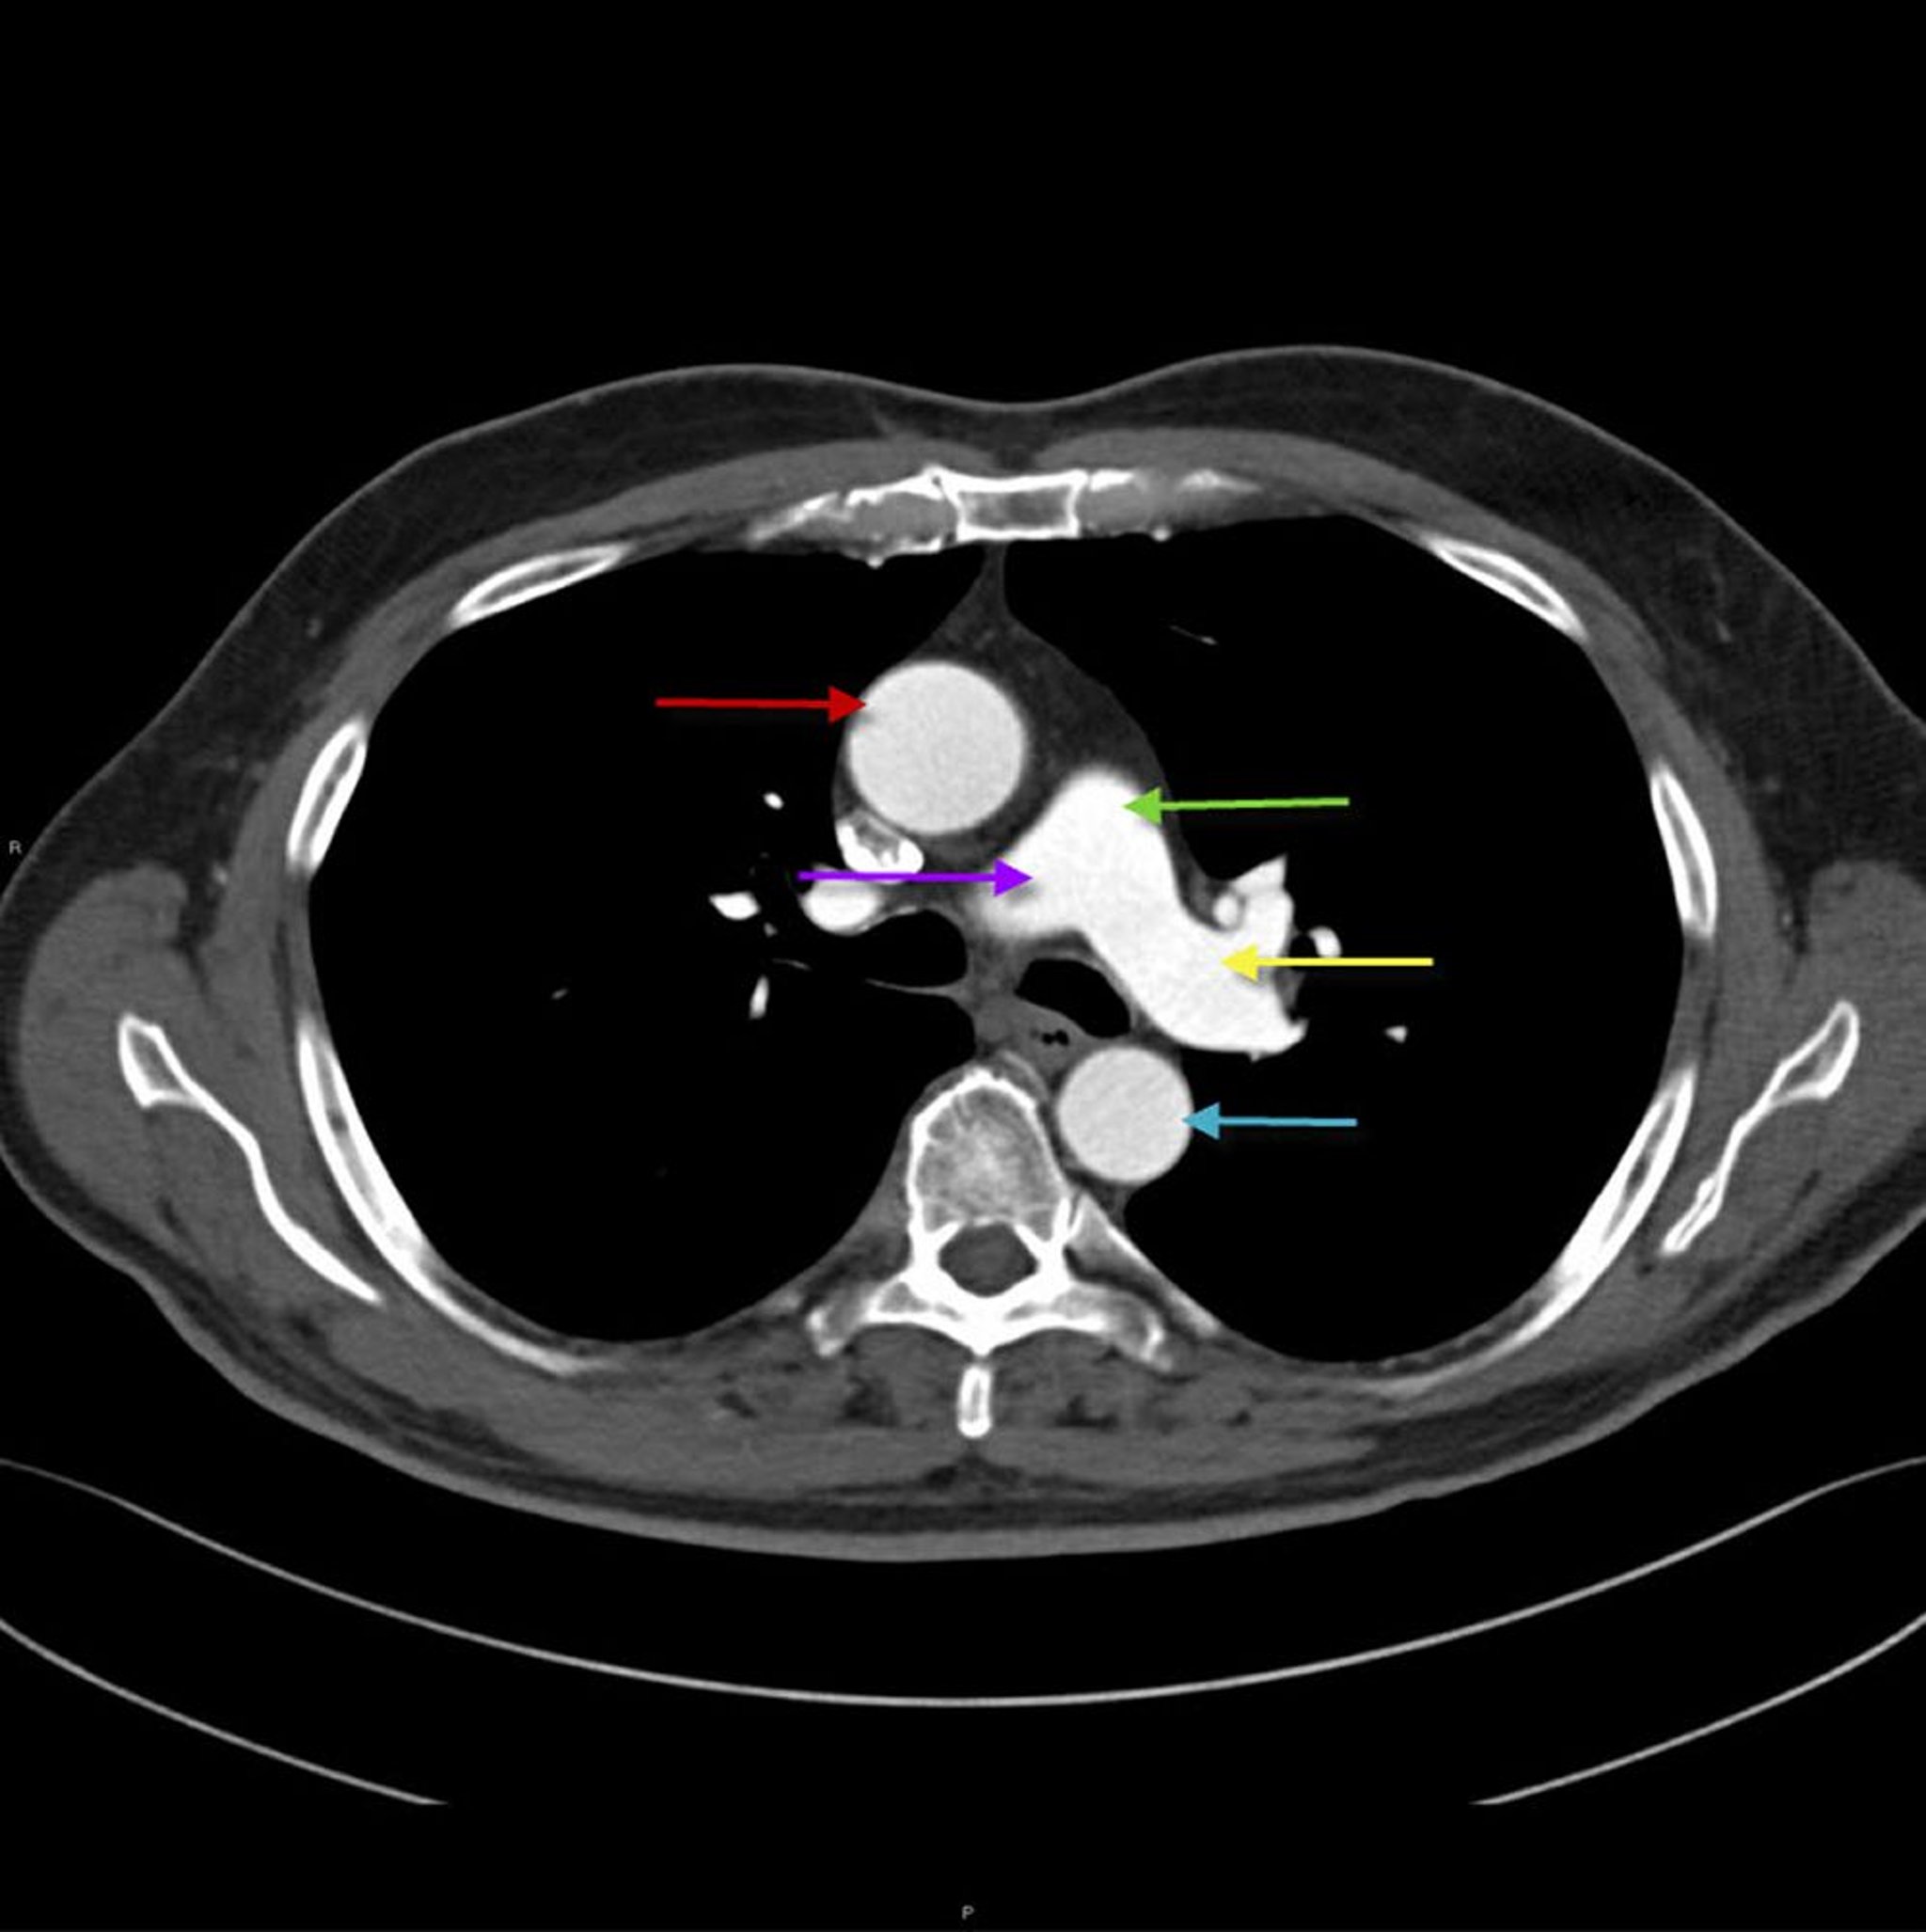

CT of Thorax Showing Anatomy of Aorta and Pulmonary Artery

This image shows the ascending thoracic aorta (red arrow) with descending thoracic aorta (blue arrow). The main pulmonary artery (green arrow) divides into the right (purple arrow) and left (yellow arrow) pulmonary artery.